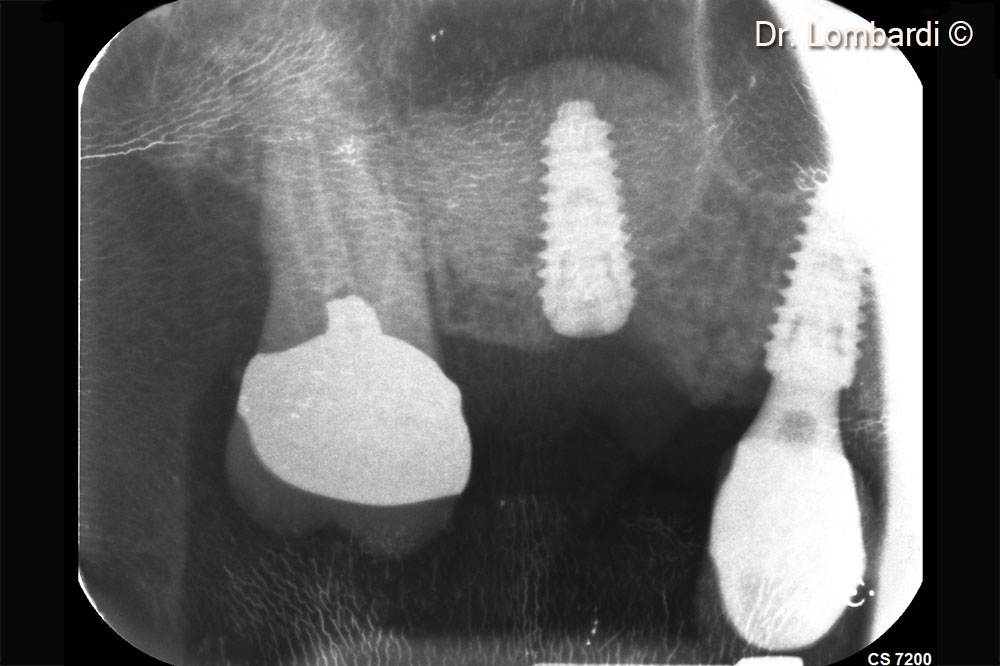

Immediate implant insertion is required to counteract the physiological biomaterial shrinkage